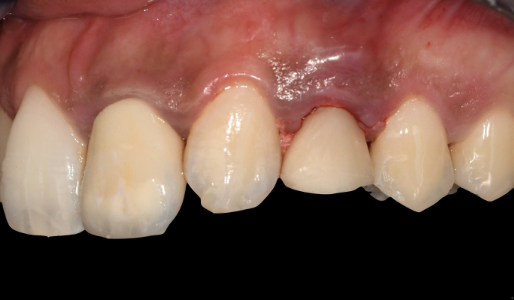

Initial clinical situation showing displaced upper left canine Initial occlusal view of the displaced canine site

Initial situation The upper left canine has drifted into the premolar space following orthodontic treatment. The decision was made to extract and place an implant, driven by the final prosthetic position.

The patient presented with agenesis (congenital absence) of the upper left first premolar and the upper right lateral incisor. Previous orthodontic treatment had addressed the spacing, and the lateral incisor site had been left unrestored. Over time, the upper left canine (UL3) had drifted significantly into the wrong position.

The decision was made to extract the displaced UL3 and place an implant at the same site — an immediate placement following extraction. This type of case demands precision: the implant position has to be driven by the final prosthetic outcome, not just the available bone. Get the angle or position wrong by a couple of millimetres and the restoration either looks wrong, functions poorly, or both.